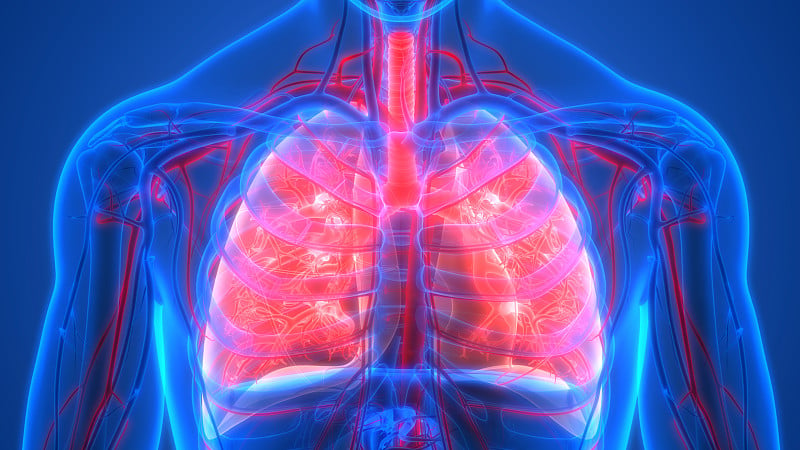

人体呼吸系统肺解剖学详情

JPG

人体呼吸系统肺解剖学详情

JPG

人体呼吸系统肺解剖学详情

JPG

人体呼吸系统肺解剖详情

JPG

人体呼吸系统肺解剖详情

JPG

人体呼吸系统肺解剖学详情

JPG

人体呼吸系统肺解剖学详情

JPG

人体呼吸系统肺解剖学详情

JPG

人体呼吸系统肺解剖学详情

JPG

人体呼吸系统肺解剖学详情

JPG

人体呼吸系统肺解剖详情

JPG

人体呼吸系统肺解剖学详情

JPG

人体呼吸系统肺解剖学详情

JPG

人体呼吸系统肺解剖详情

JPG

人体呼吸系统肺解剖详情

JPG

人体呼吸系统肺解剖学详情

JPG